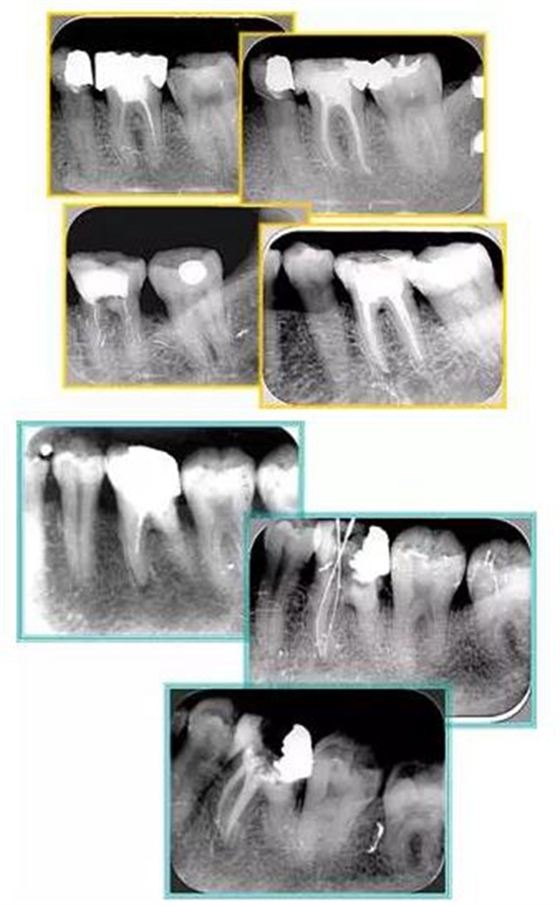

共有 4 張 X 線片,分別是術(shù)前、診斷絲 、主牙膠尖確認(rèn)、術(shù)后。

( 1 )術(shù)前:術(shù)前 X 線片用來(lái)了解牙齒的大概情況。術(shù)前預(yù)期為多根牙時(shí) X 線片應(yīng)偏頭拍攝。

( 2 )診斷絲:根據(jù)術(shù)前 X 線片進(jìn)行開(kāi)髓、根管的初步預(yù)備后,需要插入診斷絲,用來(lái)指示工作器械位置。常用 10 號(hào)或 15 號(hào)擴(kuò)大器作為診斷絲插入牙髓腔。

( 3 )主牙膠尖確認(rèn):通過(guò)術(shù)前預(yù)期和診斷絲診斷,明確工作長(zhǎng)度、牙根走向,進(jìn)行根管預(yù)備。之后應(yīng)進(jìn)行主牙膠尖(中銼)確認(rèn),已明確根管是否適合充填。

( 4 )術(shù)后:觀察治療效果。

6. 術(shù)后 X 線片

術(shù)后 X 線片用來(lái)評(píng)定根管充填 長(zhǎng)度、致密度(管壁清晰、側(cè)枝)等指標(biāo)。

左圖為根管充填術(shù)后 X 線片。圖中可見(jiàn),根管充填較好。右下圖有白色小點(diǎn),為側(cè)方加壓導(dǎo)致糊劑擠出所致,表明根管充填比較致密。

多根牙時(shí)候需進(jìn)行偏移投照,正位投照無(wú)法說(shuō)明具體哪根牙根管充填效果。

左圖和上圖為干髓治療后牙齒,齲齒疏通后進(jìn)行根管充填。

如圖為塑化加根充處理后牙齒 X 線片。

常見(jiàn)有修復(fù)性鈣化和增齡性鈣化。下面為根管鈣化 X 線片。

下圖為器械折斷的 X 線片。箭頭處示折斷器械。